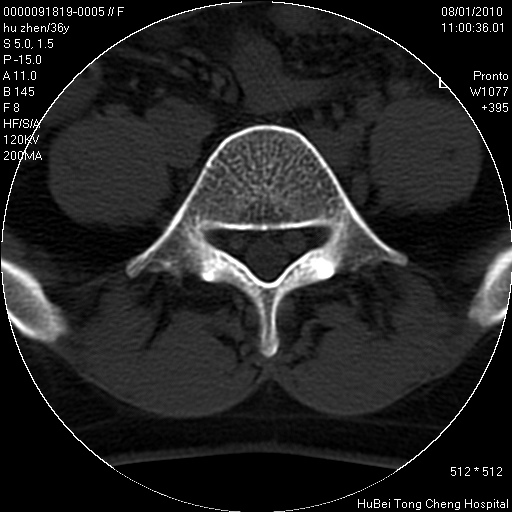

患者 女,36岁。右侧腰腿痛半月余。腰骶椎mr平扫偶然发现骶椎异常信号。

临床诊断:1)腰椎间盘突出症。2)骶椎肿瘤性病变?

骶椎ct平扫(层厚、层距均为5mm),图像如下:

良性骨病变,骨纤还是骨母细胞瘤?

考虑s1骨纤维异常增殖症。